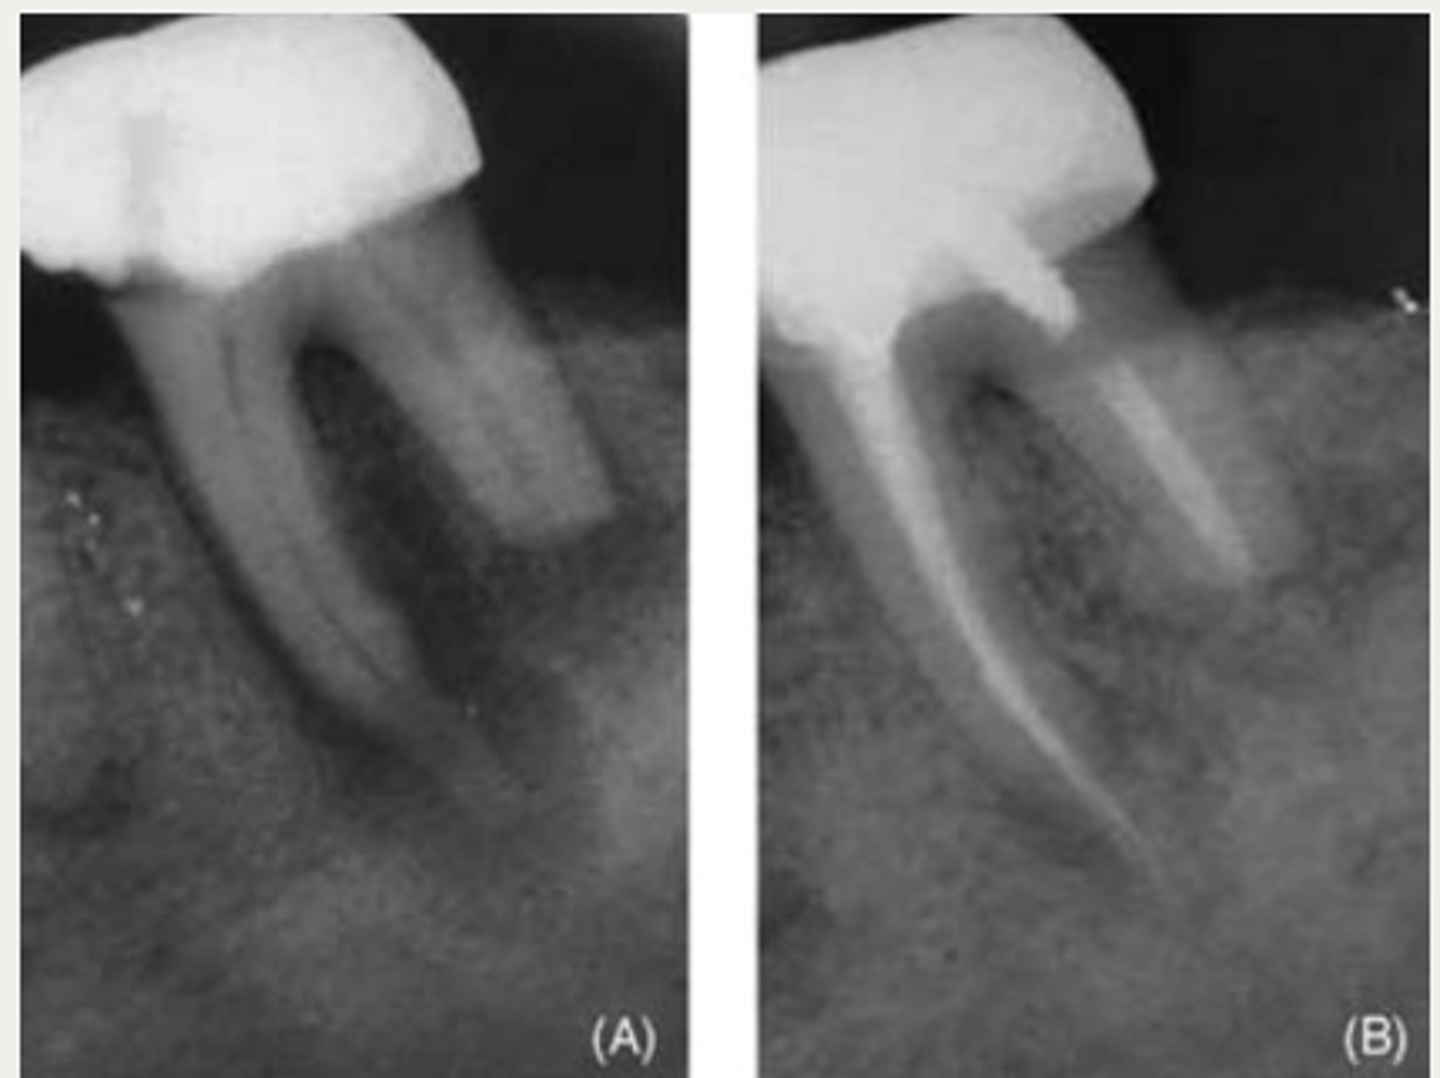

Internal replacement resorption

What type of resorption?

Metaplastic hard tissue (resembles bone/cementum)

With internal replacement resorption, what is the resorbed tissue replaced with?

It is suggested that __________ is an attempt to replaced the damaged, resorbed dentin in inflammatory internal resorption (IIR)

Which lesion has a similar diagnosis, management, and prognosis of internal inflammatory resorption (IIR) but radiographic findings will have radiopaque material in the resorptive area?